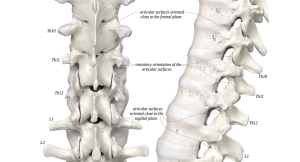

A thorakolumbalis átmenet szerepe a gerinc egészségében

Tudta, hogy a gerinc egyik legsérülékenyebb területe a háti és a deréktáji szakasz találkozása? Ez a thorakolumbalis átmenet, vagyis a T12–L1 környéke, amely biomechanikailag kulcsfontosságú szerepet játszik a gerinc mozgásában, terhelésében és sérülékenységében egyaránt.

Lokalizáció és jelentőség

A thorakolumbalis átmenet a háti (thoracalis) és deréktáji (lumbalis) régió határán helyezkedik el. Ez a zóna a merev és a mozgékony szakasz találkozása, ahol:

- a thoracalis szakasz merevebb, elsősorban rotációs mozgásokra képes,

- a lumbalis szakasz ezzel szemben mobilisabb, főként flexió–extenzió irányban aktív.

Az ízületi felszínek felépítése és orientációja

Az ízületi orientáció meghatározza, hogyan tud egy csigolyaközti szegment mozogni.

- A háti szakasz ízületi felszínei inkább coronalis (frontális) síkban állnak → elősegítik a rotációt és az oldalhajlítást.

- A lumbalis szakasz ízületei sagittalis síkúak → inkább a flexiót és extenziót engedik.

- A thorakolumbalis átmenet ezek keverékét mutatja: a felszínek orientációja egyénenként változhat, ami fokozza a szakasz sérülékenységét.

Masharawi et al., 2004 (PubMed) és Du Plessis et al., 2022 (Wiley Online Library) kimutatták, hogy az átmeneti régióban a facet-ízületi orientáció nem mindig „tiszta” thoracalis vagy lumbalis, hanem átmeneti típusú.